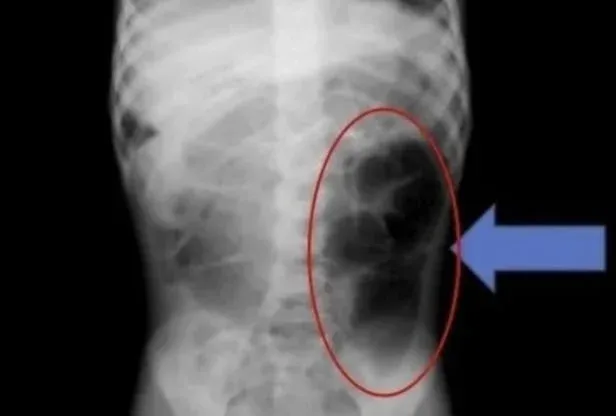

มีการรายงานกรณีหนึ่ง ในวารสารทางการแพทย์ชื่อดังอย่าง "คิวเรียส" โดยเด็กหญิงวัย 6 ขวบที่อาศัยอยู่ในประเทศซาอุดีอาระเบีย ได้เข้ารับการรักษาที่โรงพยาบาล เนื่องจากมีอาการปวดท้องเฉียบพลัน และ มีปัญหาเกี่ยวกับระบบทางเดินอาหาร หลังจากการตรวจวินิจฉัย แพทย์พบว่า "มีก้อนเส้นผมพันกันอยู่ภายในกระเพาะอาหารของเด็ก

ทีมแพทย์ยังพบว่า เส้นผมดังกล่าวไม่ได้อยู่เพียงแค่ในกระเพาะอาหารเท่านั้น แต่ยังลุกลามไปถึงลำไส้เล็กอีกด้วย โดยแพทย์กล่าวให้ข้อมูลว่า "หากผู้ป่วยเด็กมีอาการเรื้อรัง เช่น ปวดท้องซ้ำๆ อาเจียน หรือ เบื่ออาหารเป็นเวลานาน ควรพิจารณาความเป็นไปได้ ของการมีสิ่งแปลกปลอมในระบบทางเดินอาหาร"